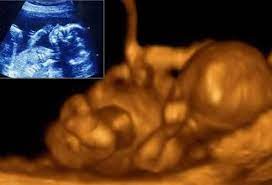

الموضح هنا هو تصوير بالموجات فوق الصوتية ثنائي الأبعاد (داخلي) بالإضافة إلى الموجات فوق الصوتية رباعية الأبعاد ، وكلاهما في الأسبوع 20.